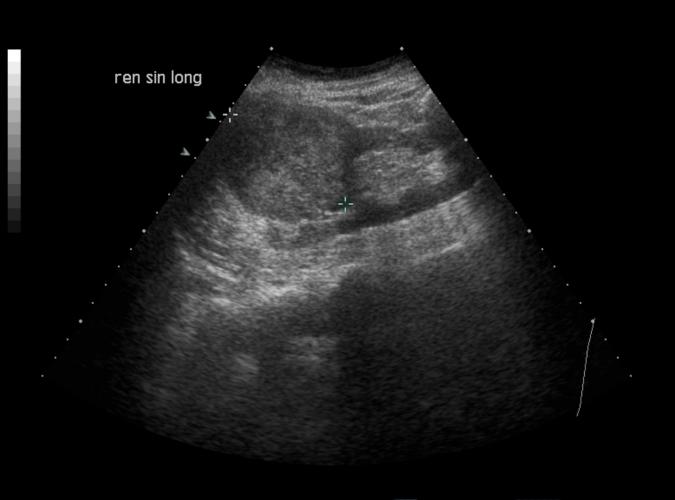

Patologi.

Long. vänster njure. Adenocarcinom utan påverkan på

njurkonturen.